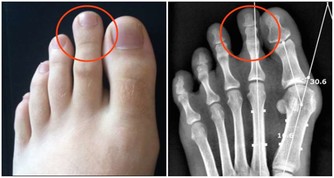

具體來說,大腸癌通常有以下症狀:便秘和腹瀉反復發生、有血便和便血、糞便很細、排便不爽、總感覺排便沒有排完全、腹部有腫塊、腹痛、有貧血症狀等等。

不過,普通人光靠自己,很難去清晰準確地判斷可能出現的這些表現。

因此,如果腹瀉持續1週以上還沒能解決,還是建議去醫院看看,找到原因,對症治療。